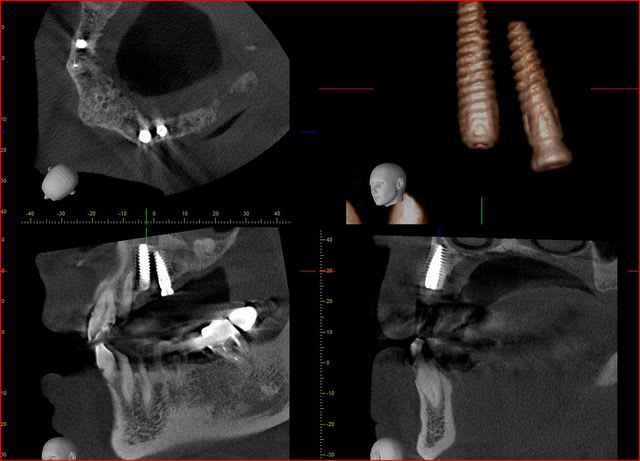

voici deux images traitées avec simplant d'un même patient la première est faite avec un Planmeca et la seconde avec Vatech

j' ai des coupes de chez morita

dés que je peux j'en mets de vatech

Capture morita 2 stjceh - Eugenol

Capture morita x66gah - Eugenol

Coupes morita fffknv - Eugenol

voila pour vatech,

le logiciel est beaucoup plus facile d'utilisation mais la précision laisse tout de même à désirer

Capture vatech s6ple1 - Eugenol

Capture vatech1 rivm62 - Eugenol

Capture vatech2 njn6uu - Eugenol

je ne me lasse pas de mon dernier joujoux...

quel précision!

implants posée le matin même..

comme on calibrait la morita, j'en ai profité pour faire un champs 10*8

je sens que je vais apprendre à poser des implants avec les contrôles post op.

Vue implant vjiqt3 - Eugenol